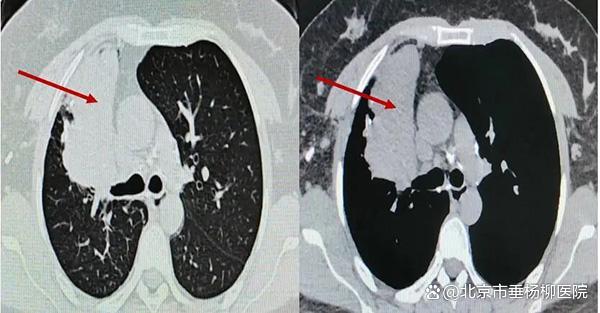

患者为36岁女性,既往有肺结核病史,近两年反复出现低热、咳嗽症状,胸部CT提示右肺上叶大片实变、坏死及多发黏液栓,气管镜显示支气管瘢痕性闭塞,化验提示曲霉菌感染。患者曾接受长期口服抗真菌药物治疗,但病灶未缩小,并出现视神经损害等药物并发症,停药后病情仍反复,右肺出现新发病灶。

▲术前胸部CT

经过系统治疗,患者低热症状消失,精神状态逐步好转。术后气管镜复查显示右上叶前段闭塞支气管已重新开放,坏死物基本清除;胸部CT显示原新发病灶消失,前段病灶引流通畅,炎症吸收良好,成功保留了右肺功能。